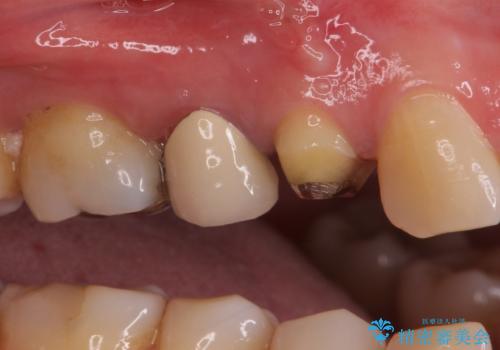

- クラウンが割れて治療を行っていたものの、途中で放置してしまったとのことで来院された患者様です。

根管治療を行った後に、ガラス系セラミッククラウンにて補綴することとしました。